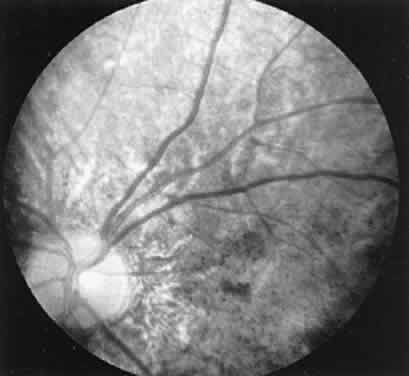

CASE 1 (FIG. 8). A 49-year-old female had poor night vision from childhood and recent difficulty going down stairs. There was no family history of any similar disorder. Vision 20/25 OD, 20/20 OS. Both fundi showed slightly pale discs, attenuated arterioles, a motheaten appearance of the retina, and peripheral bone spicules. Visual fields were 10 degrees on a Goldmann perimeter (III-4E). The ERG was extinguished.

Fig. 8. Case I. See text for details.

This is a classic case of retinitis pigmentosa with the ERG providing confirmatory evidence to the typical history, clinical picture, and visual fields.